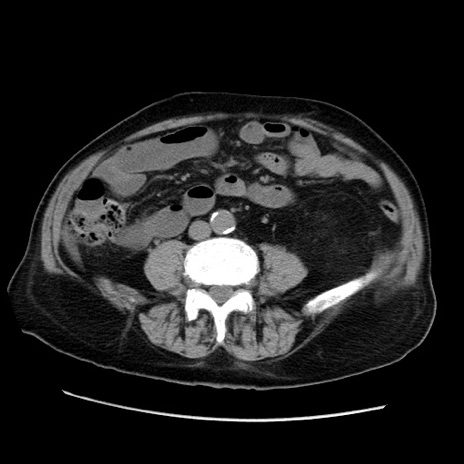

症例21(横断像)

【症例】70歳代男性

【主訴】腹痛

【現病歴】肝硬変・肝細胞癌にてかかりつけの方。約9時間前に食後より腹痛出現。症状が徐々に増悪し、嘔吐出現したため来院。

【既往歴】肝硬変、肝細胞癌(RFA、TACE後)

【身体所見】意識清明、表情苦悶様、BT 36℃、BP 129/78mmHg、P 88bpm、SpO2 97%(RA)、右上腹部から心窩部にかけて圧痛あり、反跳痛なし、筋性防御あり。

【データ】WBC 5800、CRP 0.16